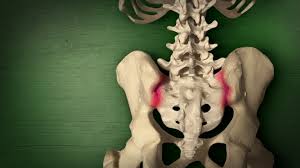

Aus funktioneller Sicht unterscheidet man zwischen einer Beckenverwringung und einer ISG-Blockade Die Beckenverwringung ist eigentlich ein normaler Prozess beim Gehen. Meist verlaufen sie einseitig aber behindern uns dennoch in der Gesamt-Beweglichkeit. Das Kreuzdarmbeingelenk wird auch als Iliosakralgelenk oder ISG bezeichnet.

Es hat sehr lange gedauert bis das behandelt wurde ich habe es erst verschleppt und dann wurde ich über Jahre nicht ernstgenommen beim Arzt sodass die Problematik mittlerweile. Ilio-Sacral-Gelenk-Block vorliegt eine Blockade des Kreuzbein-Beckenschaufel-Gelenks rechts oder links welche ebenfalls zu einer Verspannung des Beckenbodens führen kann. Das ISG auf der rechten Seite ist über einen Punkt mit dem Dünndarm verbunden.

Schwimmen bei akuten isg Schmerzen. Die ISG-Blockade verursacht sowohl ISG-Schmerzen der betroffenen Seite als auch Schmerzen die aus dem unteren Rücken über das Gesäß den hinteren Oberschenkel entlang bis zum Knie ausstrahlen können.